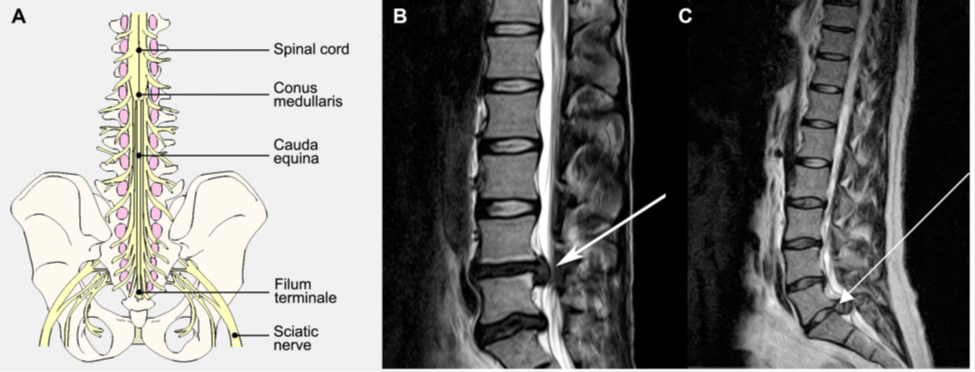

CES xảy ra do sự chèn ép các rễ thắt lưng cùng ở phía dưới L1 (hình 5), thường có biểu hiện yếu chi dưới không cân xứng, tê rần vùng đáy chậu (vùng S3-S5 chi phối), và rối loạn chức năng ruột/ bàng quang, cùng với đau lưng và rối loạn dáng đi. Cần lưu ý đánh giá tình trạng tê rần vùng đáy chậu, trương lực cơ trực tràng, và thể tích nước tiểu tồn dư sau khi tiểu tiện. Liên hệ giữa triệu chứng và hình ảnh học là rất quan trọng, vì triệu chứng có thể xảy ra cấp tính hoặc mạn tính, và thời điểm xảy ra triệu chứng có ý nghĩa quan trọng trong quyết định phẫu thuật. CES cấp cứu xảy ra ở BN có khiếm khuyết thần kinh cấp tính hoặc tiến triển trong 1-2 ngày. Chèn ép do thoát vị đĩa đệm cấp, nhiễm trùng, và xuất huyết (tự phát hoặc sau mổ) là những khả năng có thể xảy ra. CES hiếm khi xảy ra, tỷ lệ 1:65 000 bệnh nhân và chỉ khoảng 1-2% BN thoát vị đĩa đệm. Cần phân biệt CES với hội chứng chóp tủy, là hội chứng xảy ra do chèn ép chóp tủy với biểu hiện yếu hai chi, tê rần đáy chậu, và rối loạn chức năng ruột. CES cũng có thể xảy ra do gãy đốt sống hoặc u.

Hình 5. Thoát vị đĩa đệm gây CES. A. Sơ đồ chùm đuôi ngựạ với chóp tủy ở ngang L1. B. Thoát vị đĩa đệm ở L4L5 hoặc C. L5S1 gây chèn ép chùm đuôi ngựa.